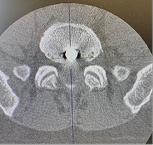

15.07.2025 г. проведена операция: эндоскопическая бипортальная ревизия, санация, удаление осколка из межтелового промежутка на уровне L5-S1 позвонков. Операция выполнена через два минимальных разреза по 0,7 см на уровне ранения. Под контролем флюороскопии в соответствии с методикой сформирован порт для эндоскопа и второй порт для рабочего инструмента. Операция выполнялась в водной среде под постоянной ирригацией физиологическим раствором. В ходе операции осуществлен атравматичный бескровный доступ к проблемному уровню без скелетирования (без рассечения) паравертебральных мышц. При помощи специального эндоскопического инструментария поэтапно, в соответствие с методикой, визуализирован проходящий S1 корешок и дуральный мешок, задняя продольная связка, осуществлен доступ к осколку. Последний выделен при помощи Г-образного крючка и удален при помощи конхотомов. Выделение и удаление осколка не сопровождалось тракцией невральных структур. Ход операции, начиная от доступа, внешний вид интраоперационной раны до и после удаления осколка представлены на фото.

Рис. 2. Этап доступа и внешний вид операционной раны кожи и на ЭОП-контроле.